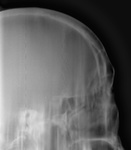

Томограммы.

Томограммы в прямой проекции, правда "хреновые" - три среза.